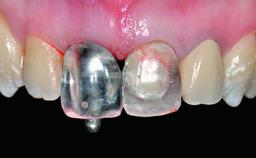

Abutment Type CAD/CAM

Prosthesis Type FDP

Retention Cemented, with prosthesis margin < 3mm submucosal Cemented, with prosthesis margin < 3mm submucosal

Provisional Implant-Supported Prosthesis Prosthodontic margin > 3 mm apical to mucosal margin Prosthodontic margin > 3 mm apical to mucosal margin